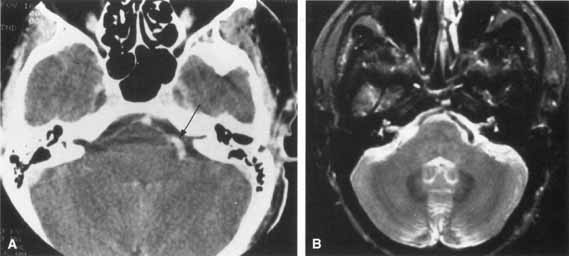

Fig. 12 Axial T1-weighted, gadolinium-enhanced MRI showing bilateral proximal facial nerve enhancement (arrows) in patient with Lyme disease and facial diplegia.